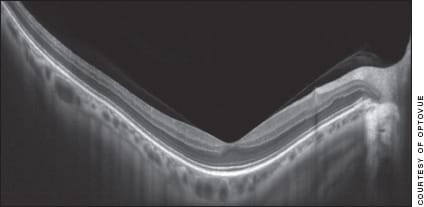

Figure 4. An -18 D myope imaged by SD-OCT, again with subtle details visible.